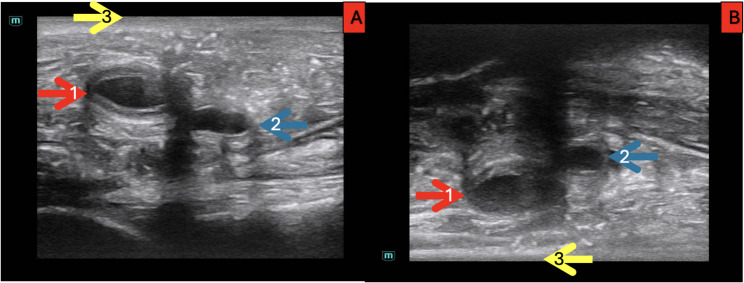

Background: Ultrasound-guided vascular access (USGVA) is an essential clinical skill, but novice learners often face difficulties in interpreting ultrasound images and achieving spatial alignment during procedures. To address this challenge, we hypothesized that using a reversed screen orientation could facilitate the learning process. Reversed screen orientation refers to an ultrasound image flipped in the transverse plane, producing a top-to-bottom mirror image by activating the "reverse" function on the ultrasound (US) device. We assumed that this configuration might help align the visual trajectory of the needle with the user's hand movements, potentially easing spatial perception during the early stages of learning.

Metods: The study was conducted in the Anatomy Laboratory of Ordu University Medical Faculty with 60 final-year medical students with no prior US experience. Participants were randomly divided into two groups (A and B), who performed femoral vein needle punctures on cadavers under US guidance with standard (Group A) and reverse (Group B) screen. Each group used both screen orientations across two attempts. Before the procedure, students received theoretical training. Data collected included demographic information, needle visibility, procedure duration, success rates, and complications. Statistical analyses were performed using Statistical Package for the Social Sciences (SPSS), and significance was set at p < 0.05.

Results: The results showed no significant differences in age or sex distribution between groups. In the first attempt, 83.3% of participants with posterior wall penetration were in Group A (standard screen orientation). Needle visualibity score was higher in Group B (reversed screen orientation). The perceived ease of the procedure showed a significant difference in favor of Group B in the second attempt. Overall, while the success rates and time taken were similar between groups, Group B exhibited improved needle visualization and fewer complications related to posterior wall penetration.